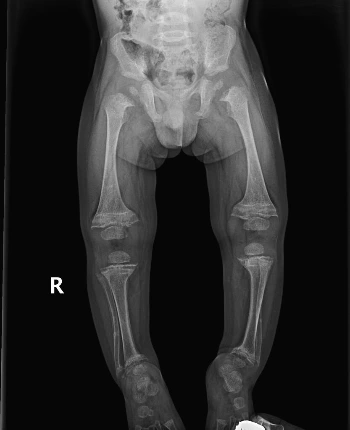

생후 6개월 아이인데 다리가 오다리예요.

아직 걸음마를 시작하지도 못한 아이들에 있어서 오다리는 흔하다. 일단 신생아는 태어나면 오다리인 게 정상이다. 우리가 신생아의 신체비율 (머리가 크고 상대적으로 몸통이 작은 것)을 보고 문제가 있다, 머리가 크다라고 하지 않듯이)이 성인과 다르다고 하여 문제가 있다고 생각하지 않는 것과 같다. (아이가 신생아일 때 전신을 찍은 사진을 찾아보면 대부분 다리가 휘어져 있을 것이다.)

다만 모유 수유를 하는 경우와 일부 경우에 있어서 소위 구루병이라고 하는 비타민 디의 부족으로 다리가 휘어지는 경우와 우리나라에서는 흔하지 않지만 Blount disease라 하여 성장판의 부분 이상으로 다리가 휘는 경우가 있다. 대부분의 경우는 신생아일 때 아이들이 기저귀를 입고 찍은 사진이 있을 텐데 오다리가 오히려 점점 더 심해지는 양상이거나, 돌이 지나서도 오다리가 있는 경우에는 다른 질환의 감별을 위하여 병원에 방문하는 것을 권한다.

아래 영상은 구루병 환자의 영상으로 성장판이 일반적인 단순 오다리와는 다른 모양을 보인다.

rickets X-ray.jpeg https://radiopaedia.org/cases/rickets-26